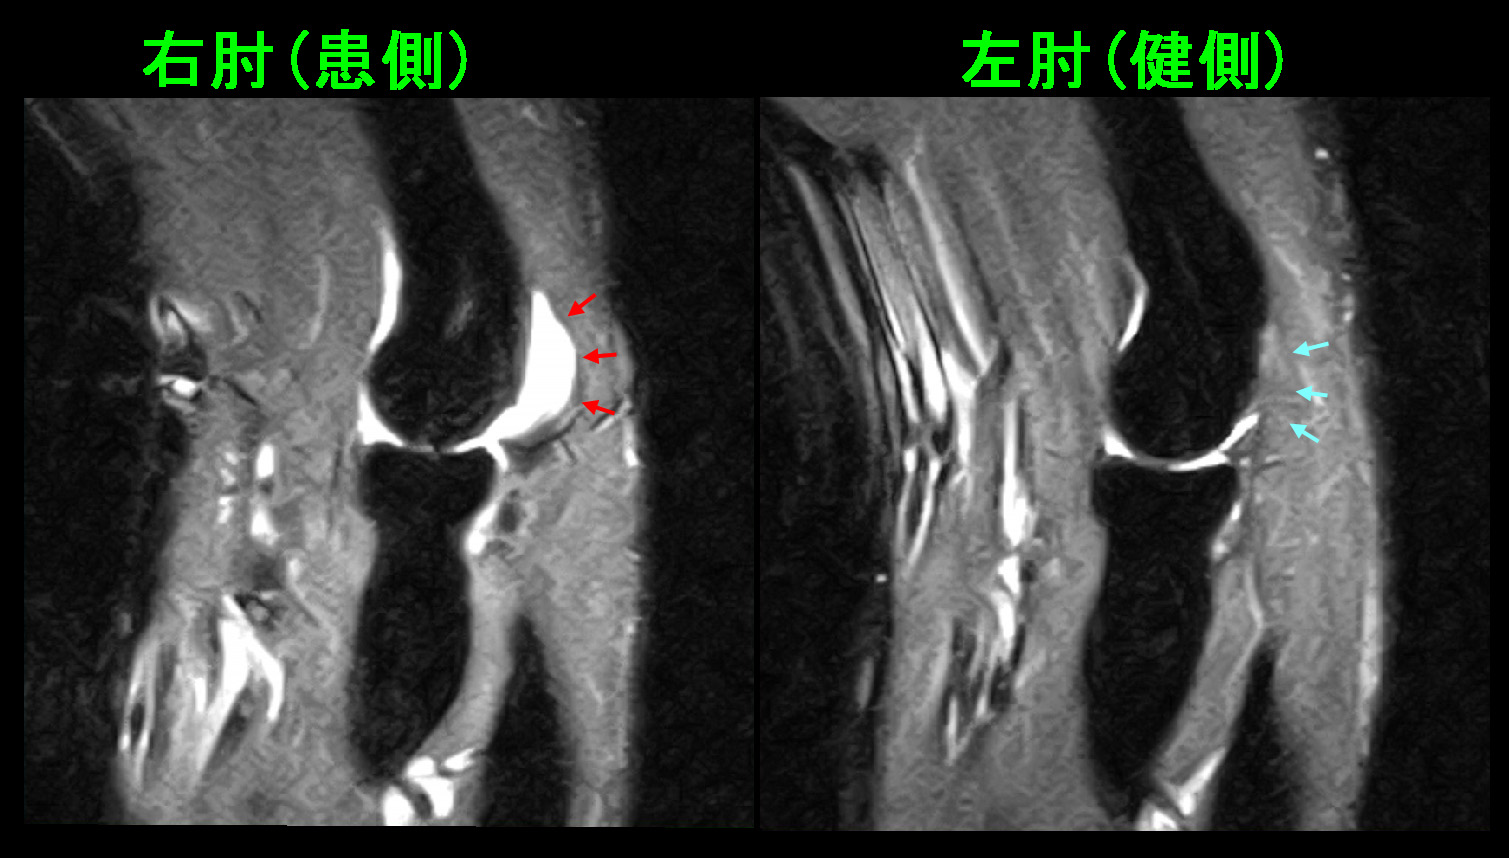

38才男MRI2.jpg

このMRI画像では赤矢印の橈骨頭部は右肘に比して骨折により広がっていて、関節面は陥凹していることが分かります。